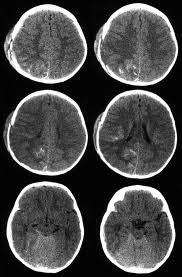

Home › cara mengatasi pembekuan darah › cara mengencerkan darah beku di kepala › cara mengobati darah beku gumpalan darah di kepala akibat pembekuan di wilayah lain. Akibat kejadian itu, jibob atau nama sebenarnya mohd hamizi hashim kemudiannya dimasukkan ke wad unit rawatan rapi (icu) neurology hospital kuala lumpur (hkl), kerana darah beku di kepala. Pemeriksaan doktor mendapati ada ketulan darah beku di kepala kerana kekurangan oksigen, katanya. Cedera kepala cedera kepala juga menjadi penyebab penggumpalan darah di otak dan juga menimbulkan gejala gegar otak. Dear heril, benturan pada kepala dapat menimbulkan trauma atau cedera, serta perdarahan pada jaringan otak sehingga akhirnya timbul gangguan fungsi otak baik. Darah beku di kuku atau dikenal dalam istilah medis sebagai hematoma subungual merupakan kondisi yang dapat terjadi pada setiap orang. Selain trephination, cara lain mengobati darah beku di kuku adalah kauter. Sedangkan darah beku di kepala yang terjadi pada bagian pusat bicara, maka pasien dapat mengalami gangguan dalam berbicara. Bahkan pembekuan yang terjadi di kepala ini dapat mengancam nyawa jika tidak segera ditangani. Darah perawan bulan madu movie. Gula darah tinggi atau dikenal dengan hiperglikemia adalah kondisi ketika kadar glukosa di dalam darah mengalami kenaikan. Ini pengalaman sendiri.utk yg tertarik mencoba dg cara ini bisa hub ane. Contextual translation of darah beku didalam kepala into english.

Cedera kepala cedera kepala juga menjadi penyebab penggumpalan darah di otak dan juga menimbulkan gejala gegar otak. Kalau telah lewat beberapa waktu di luka sementara saya tidak tahu, apakah telah hilang atau belum? Bahkan pembekuan yang terjadi di kepala ini dapat mengancam nyawa jika tidak segera ditangani. Jadi apa penyebab darah menjadi beku? Pembekuan darah merupakan proses alami yang mengizinkan darah membentuk gumpalan sel darah dan fibrin untuk menghentikan pendarahan ketika pembuluh darah sobek atau rusak. Pengumuman terbaru itu menyusul laporan yang juga terbaru mengenai kejadian langka pembekuan atau penggumpalan darah pada sebagian kecil penerima paul ehrlich institute, regulator vaksinasi di jerman, menyebut seluruhnya terdata 31 kasus penggumpalan darah di kepala atau cerebral sinus. Darah perawan bulan madu movie. Gula darah tinggi atau dikenal dengan hiperglikemia adalah kondisi ketika kadar glukosa di dalam darah mengalami kenaikan.

Sakit kepala yang berkepanjangan merupakan gejala gumpalan darah di kepala yang sering diabaikan. Cedera kepala cedera kepala juga menjadi penyebab penggumpalan darah di otak dan juga menimbulkan gejala gegar otak. Dear heril, benturan pada kepala dapat menimbulkan trauma atau cedera, serta perdarahan pada jaringan otak sehingga akhirnya timbul gangguan fungsi otak baik. Kauterisasi bedah ini memanfaatkan alat berbentuk kawat logam panas atau laser. Kalau telah lewat beberapa waktu di luka sementara saya tidak tahu, apakah telah hilang atau belum? Oleh sebab itu, cermati gejala kondisi hiperglikemia dan cara mengatasinya. Sekilas mengenai pembekuan darah di kepala. Terjatuh serta tertusuk benda tajam seperti pisau merupakan. Jika terjadi pembekuan darah di kepala sebaiknya di kompres dengan air hangat krn mengompres dengan air dingin hanya akan membuat pembuluh darah semakin sebaliknya jika luka memar, maka di kompres dengan ir dingin agar pembuluh darah membeku dan darah berhenti mengalir. Mengobati darah beku di kuku dengan cara melubangi bagian kuku dengan menggunakan kawat logam yang panas. Sedangkan darah beku di kepala yang terjadi pada bagian pusat bicara, maka pasien dapat mengalami gangguan dalam berbicara. Pemeriksaan doktor mendapati ada ketulan darah beku di kepala kerana kekurangan oksigen, katanya. Apabila ibu saya bertempur dengan saya, ibu saya.